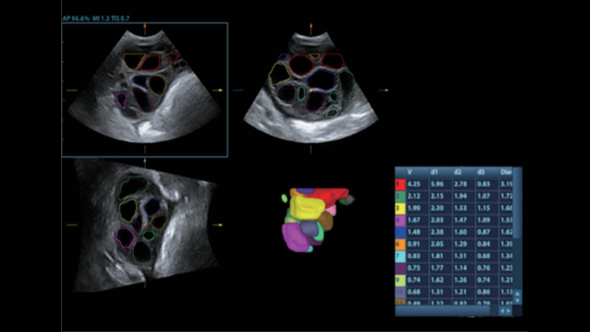

–ü―Ä–Β–¥–Ϋ–Α–Ζ–Ϋ–Α―΅–Β–Ϋ–Η–Β DC-80 EXP ―¹–Ψ―¹―²–Ψ–Η―² –≤ ―²–Ψ–Φ, ―΅―²–Ψ–±―΄ –Ω–Ψ–Φ–Ψ–≥–Α―²―¨ –£–Α–Φ ―¹–Ω–Ψ–Κ–Ψ–Ι–Ϋ–Ψ ―Ä–Β–Α–≥–Η―Ä–Ψ–≤–Α―²―¨ –Ϋ–Α ―É―¹–Μ–Ψ–Ε–Ϋ―è―é―â–Η–Β―¹―è –¥–Β–Ϋ―¨ –Ψ―²–Ψ –¥–Ϋ―è –Κ–Μ–Η–Ϋ–Η―΅–Β―¹–Κ–Η–Β –Ζ–Α–¥–Α―΅–Η, –Ω―Ä–Β–¥–Ψ―¹―²–Α–≤–Μ―è―è –Ω―Ä–Β–≤–Ψ―¹―Ö–Ψ–¥–Ϋ–Ψ–Β –Κ–Α―΅–Β―¹―²–≤–Ψ –≤–Η–Ζ―É–Α–Μ–Η–Ζ–Α―Ü–Η–Η, –Ω–Β―Ä–≤–Ψ–Κ–Μ–Α―¹―¹–Ϋ―΄–Β –Η–Ϋ―²–Β–Μ–Μ–Β–Κ―²―É–Α–Μ―¨–Ϋ―΄–Β ―Ä–Β―à–Β–Ϋ–Η―è –Η –Φ–Ϋ–Ψ–≥–Ψ–Β –¥―Ä―É–≥–Ψ–Β βÄΠ

–£–Ϋ–Β–¥―Ä–Β–Ϋ–Η–Β –≤ DC-80 EXP –¥–Α―²―΅–Η–Κ–Ψ–≤ ―¹–≤–Β―Ä―Ö–≤―΄―¹–Ψ–Κ–Ψ–Ι –Ω―Ä–Ψ–Η–Ζ–≤–Ψ–¥–Η―²–Β–Μ―¨–Ϋ–Ψ―¹―²–Η –Ψ–±–Β―¹–Ω–Β―΅–Η–≤–Α–Β―² –¥–Μ―è –£–Α―¹ –Ω―Ä–Β–≤–Ψ―¹―Ö–Ψ–¥–Ϋ–Ψ–Β –Κ–Α―΅–Β―¹―²–≤–Ψ –≤–Η–Ζ―É–Α–Μ–Η–Ζ–Α―Ü–Η–Η.

–ë–Μ–Α–≥–Ψ–¥–Α―Ä―è ―¹–Ψ―΅–Β―²–Α–Ϋ–Η―é ―²–Β―Ö–Ϋ–Ψ–Μ–Ψ–≥–Η–Η 3–Δ? (–Δ―Ä–Ψ–Ι–Ϋ–Ψ–Ι ―¹–Ψ–≥–Μ–Α―¹―É―é―â–Η–Ι ―¹–Μ–Ψ–Ι, ―²–Β―Ö–Ϋ–Ψ–Μ–Ψ–≥–Η―è –Ω–Ψ–Μ–Ϋ–Ψ―¹―²―¨―é ―Ä–Α–Ζ–¥–Β–Μ–Β–Ϋ–Ϋ―΄―Ö –Κ―Ä–Η―¹―²–Α–Μ–Μ–Ψ–≤, ―²–Β―Ä–Φ–Ψ–Κ–Ψ–Ϋ―²―Ä–Ψ–Μ―¨ –Α–Κ―É―¹―²–Η―΅–Β―¹–Κ–Ψ–Ι –Μ–Η–Ϋ–Ζ―΄) –Η –Φ–Ψ–Ϋ–Ψ–Κ―Ä–Η―¹―²–Α–Μ–Μ–Η―΅–Β―¹–Κ–Η―Ö –¥–Α―²―΅–Η–Κ–Ψ–≤ –Ψ–±–Β―¹–Ω–Β―΅–Η–≤–Α–Β―²―¹―è –Κ–Α–Κ –±–Ψ–Μ–Β–Β –≤―΄―¹–Ψ–Κ–Α―è ―Ä–Α–Ζ―Ä–Β―à–Α―é―â–Α―è, ―²–Α–Κ –Η –Ω―Ä–Ψ–Ϋ–Η–Κ–Α―é―â–Α―è ―¹–Ω–Ψ―¹–Ψ–±–Ϋ–Ψ―¹―²―¨, –≤ ―Ä–Β–Ζ―É–Μ―¨―²–Α―²–Β ―΅–Β–≥–Ψ ―Ä–Β―à–Α–Β―²―¹―è –Ω―Ä–Ψ–±–Μ–Β–Φ–Α –Η―¹―¹–Μ–Β–¥–Ψ–≤–Α–Ϋ–Η–Ι ―²–Β―Ö–Ϋ–Η―΅–Β―¹–Κ–Η ―¹–Μ–Ψ–Ε–Ϋ―΄―Ö –Ω–Α―Ü–Η–Β–Ϋ―²–Ψ–≤.

–Θ–Μ―¨―²―Ä–Α–Μ–Β–≥–Κ–Η–Ι –Η –≤―΄―¹–Ψ–Κ–Ψ–Ω–Μ–Ψ―²–Ϋ―΄–Ι –Ψ–±―ä–Β–Φ–Ϋ―΄–Ι –¥–Α―²―΅–Η–Κ –Ψ–±–Β―¹–Ω–Β―΅–Η–≤–Α–Β―² –Ω―Ä–Β–≤–Ψ―¹―Ö–Ψ–¥–Ϋ–Ψ–Β –Κ–Α―΅–Β―¹―²–≤–Ψ –≤–Η–Ζ―É–Α–Μ–Η–Ζ–Α―Ü–Η–Η –≤ –Α–Κ―É―à–Β―Ä―¹―²–≤–Β –≤ ―Ä–Β–Ε–Η–Φ–Α―Ö 2D, –Π–î–ö, 3D/4D –¥–Μ―è –±–Ψ–Μ―¨―à–Β–Ι –¥–Η–Α–≥–Ϋ–Ψ―¹―²–Η―΅–Β―¹–Κ–Ψ–Ι ―É–≤–Β―Ä–Β–Ϋ–Ϋ–Ψ―¹―²–Η –Η –Ω–Ψ–≤―΄―à–Β–Ϋ–Η―è –Κ–Α―΅–Β―¹―²–≤–Α –Η―¹―¹–Μ–Β–¥–Ψ–≤–Α–Ϋ–Η―è;